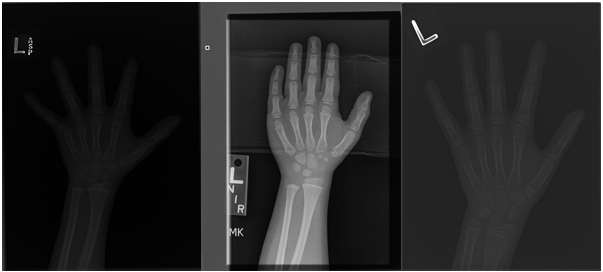

However, adversarial learning is typically applied in classification problems. The binary cross-entropy in Eq. 3 is also frequently used in improving the accuracy of classification problems. The cross-entropy loss is not proper to indicate the data difference in a regression problem. Therefore, we need a regression loss function to distinguish the training and test datasets, and we adopt the adversarial learning for the regression problem as follows.

where is adversarial regression loss, is the mapping from training to test data; is the adapted data regressor, and contains all training and test samples; is the data label in Fig. 2, specifically, is the label for the training data and is the label for the test data; is the prediction of data label; and denote the mean actual and predicted values of training or test dataset and is a small number (1e-9) to prevent division by 0. can measure how well-matched the training and test data are from both individual and overall differences. A perfect regression model would have an adversarial regression loss of 0.

To this end, the data regressor learns the data discrepancy by maximizing adversarial regression loss with the fixed , and the feature extractor aims to learn domain-invariant representations via minimizing with the optimal regressor . Eq. LABEL:eq:regre guarantees that , that is, given training samples, it will learn a map from training to test samples, while minimizing the in Eq. 2. However, Eq. LABEL:eq:regre only guarantees training data close to test data, and it does not ensure that maintains the features of the training samples. We hence introduce another mapping from test data to training data and train it with the same adversarial regression loss as in as shown in Eq. 5. The only difference is that the is the new data label for training data, and is the new data label for test data.

To encourage the training and test information to be preserved during the adversarial regression learning, we propose a feature reconstruction loss in our model. Details of the feature reconstruction layers are shown in Fig. 3; the reconstruction layers are right behind the shared layers, and it aims to reconstruct extracted features and maintain feature consistency during the conversion process without losing features. The feature reconstruction loss is defined as: